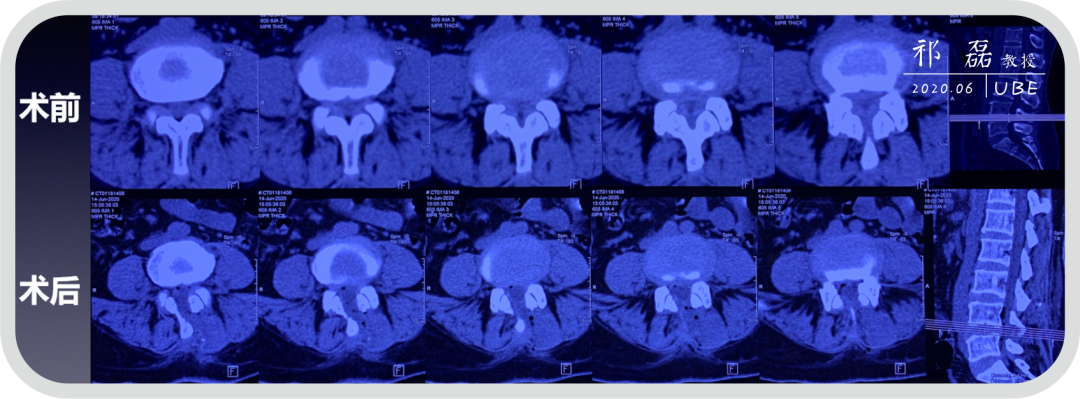

患者:吴某,女,53岁,腰痛及双下肢疼痛麻木5年余,加重1月余,间歇性跛行约200米。于近日入我院查体,下腰椎棘突及椎旁肌深压痛,双下肢感觉运动正常。双侧直腿抬高试验(-),双侧踝反射(-),入院诊断为:腰椎管狭窄症。

图2:腰椎CT

图7:术后即刻CT

图9:术前术后CT对比